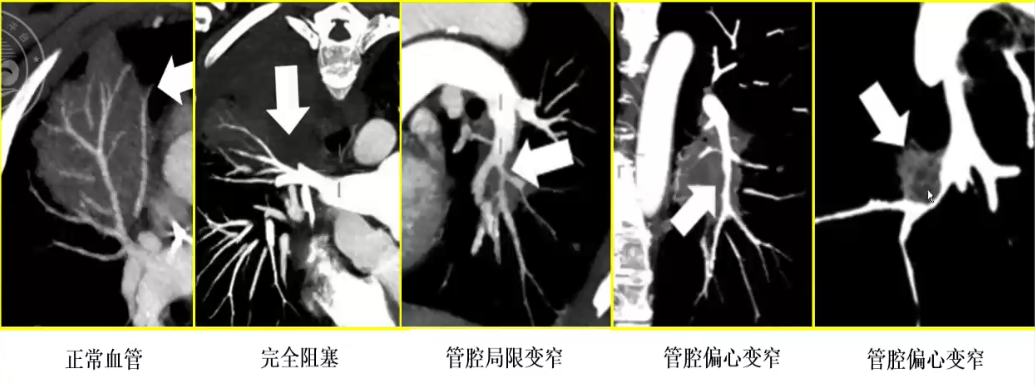

肺血管租塞征

❖ 定义:真菌感染侵袭血管导致血栓形成,造成局限性浸润灶内血管中断,类似于肺栓塞

❖ VOS适用病灶:结节大于10mm,楔形病灶大于12mm

❖ 在粒缺和非粒缺真菌感染患者中,VOS的敏感性和特异性均较高,VOS阴性可以排除一部分真菌感染

❖ 血液系统恶性肿瘤患者中,VOS阳性诊断真菌感染的敏感性和特异性均较其他(HS,RHS,HyS)征象高,VOS阴性提示应停止早期经验性抗真菌治疗